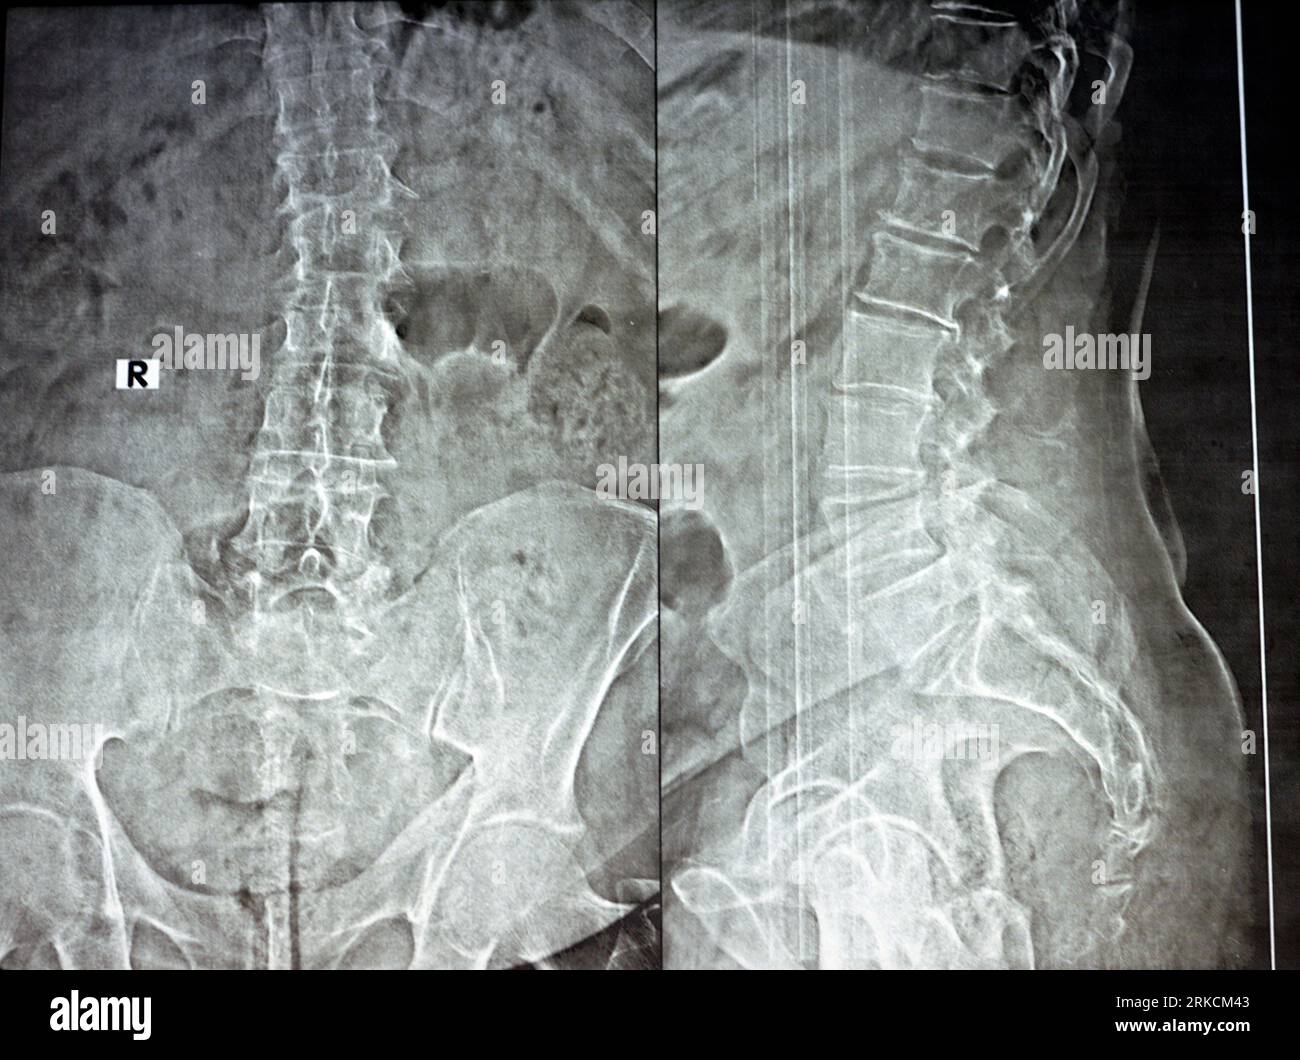

Espina Iliaca Antero Inferiorr Radiografia . Web subspine hip impingement is characterized by the prominent or abnormal morphology of the anteroinferior iliac spine (aiis), which contributes to the. Web aiis are identified based on the relationship between the distal extension of the acetabular rim and the aiis.

Web espina ilíaca anteroinferior (eiai): Web the anterior inferior iliac spine (aiis) is a rough bony projection on anterior border of the ilium of the hip, inferior to the. The anterior inferior iliac spine (aiis) prominence is increasingly recognized in the setting of femoroacetabular impingement (fai).

The anterior inferior iliac spine (aiis) prominence is increasingly recognized in the setting of femoroacetabular impingement (fai). Web the anterior inferior iliac spine is a bony prominence located on the anterior margin of the ilium, positioned below the anterior. Web this is a common pelvic avulsion fracture, that occurs due to sudden forceful hip extension while contraction of the straight head of the. Web espina ilíaca anteroinferior (eiai):